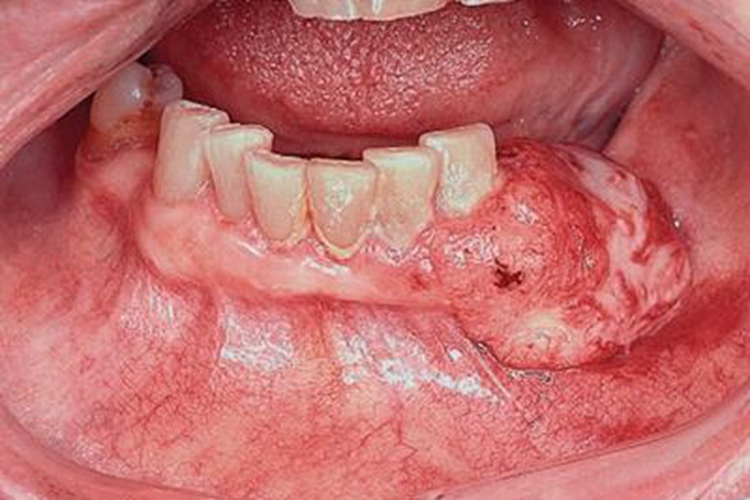

牙龈癌可导致牙龈局部出现形状不规则的肿物,大小不一,呈淡红色、粉白色。

牙龈癌可导致牙龈局部出现大小不一的肿物,形状不规则,凸起于牙龈表面,呈淡红色、粉白色,表面凹凸不平,触之易出血。牙龈上的肿物可以侵犯牙槽突骨膜及骨质,进而出现牙松动,并可发生脱落。